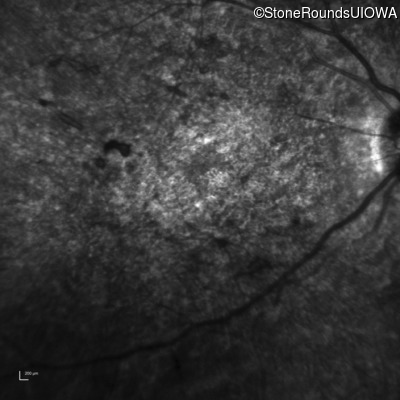

Infrared Fundus Photograph - Left - 20/250 sc

Exemplar